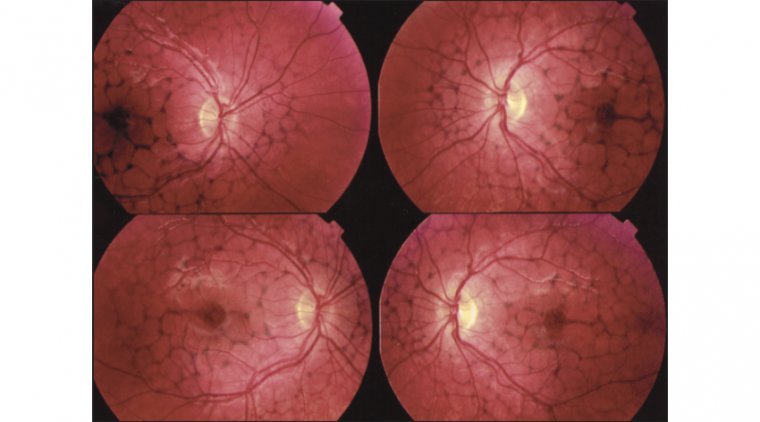

Retinal pattern dystrophies, as the name implies, are a group of disorders characterized by diverse pigment deposition patterns in the macula’s retinal pigment epithelium (RPE). The RPE, located in the retina’s outermost layer, is rich in pigment particles, such as melanin and lipofuscin, that prevent light damage. A yellowish, orange, or brown lipofuscin accumulation in the subretinal region characterizes many pattern dystrophies. Typically, these dystrophies are associated with a favorable visual prognosis; however, gradual central vision loss remains a possibility.

1. Adult-onset foveomacular vitelliform dystrophy: It is the most prevalent kind of pattern dystrophy. It is characterized by bilateral, symmetrical, grayish-yellow, round lesion within macular region. The lesion is typically one-third to one-half the diameter of a disc.

2. Butterfly-shaped pattern dystrophy: It is commonly observed between the second and fifth decades of life. They manifest as yellow and melanin pigmentation in the fovea, typically in a spoke-like or butterfly-wing-like configuration.

3. Reticular dystrophy is usually seen in the 5th decade of life. Clinically, it features a network of pigmented lines and knots in a fish net-like appearance in the RPE. Lesions are up to five-disc diameters from the macula and typically fade with age.

4. Multifocal Pattern Dystrophy includes multiple irregular white-yellow specks dispersed across the macula, comparable to the flecks in Stargardt disease.

5. Fundus Pulverulentus: Fundus pulverulentus is characterized by a granular appearance and punctiform mottling of the retinal pigment epithelium (RPE) within the macula. Due to the RPE mottling, Fundus pulverulentus might be confused for age-related macular degeneration; however, OCT imaging can help differentiate the two.